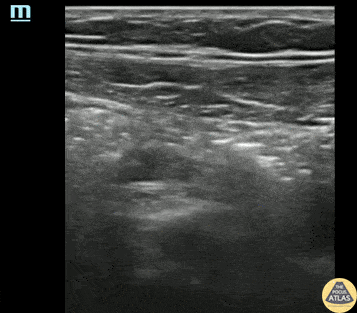

A teenaged female presented with lower abdominal pain, and underwent POCUS to evaluate for appendicitis. A normal appendix was visualized. Seen here, the appendix is seen as a blind ending pouch with a hyperechoic outer border, a relatively hypoechoic wall, and relatively hyperechoic contents. The normal appendix should be less than 7cm in diameter and should be compressible. This patient ultimately was diagnosed with an alternate etiology of her abdominal pain. Dr. Molly Thiessen Denver Health Medical Center